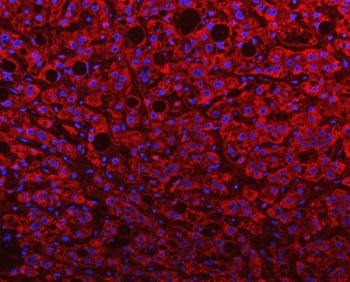

Immunofluorescent staining of FFPE human liver cancer with PGP antibody (red) and DAPI nuclear stain (blue). HIER: steam section in pH8 EDTA buffer for 20 min.